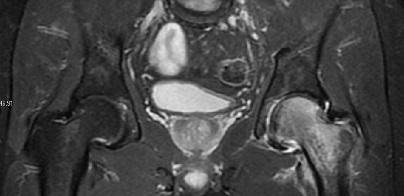

Plain radiographs may show a decrease in bone density compared to the opposite side, but MRI is diagnostic — showing diffuse marrow oedema and a large joint effusion. Treatment is symptomatic until the condition improves. Oral bisphosphonates can decrease pain and improve bone density relatively quickly. As the circulation is not affected, intra-osseous injection is not required.

MRI of the pelvis showing diffuse edema in the left proximal femur

MRI of the pelvis showing diffuse oedema in the left proximal femur.